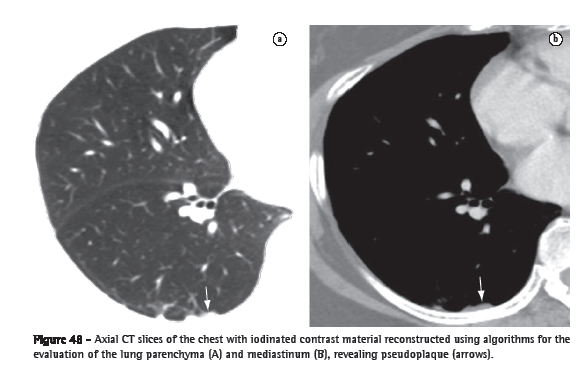

Pseudoplaque (pseudoplaca)

A pseudoplaque is a peripheral pulmonary opacity, adjacent to the visceral pleura and formed by small, coalescent pulmonary nodules that simulate the pleural plaque (Figure 48).(73) It is more commonly found in sarcoidosis, silicosis and coal workers' pneumoconiosis.